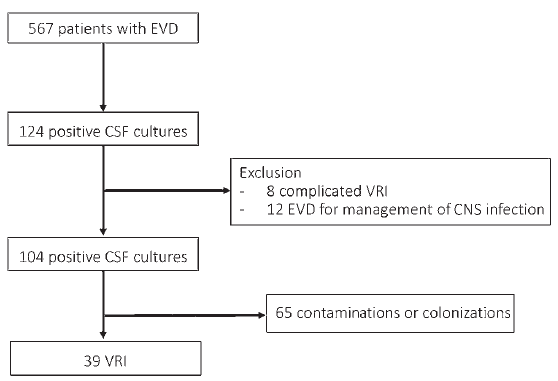

本研究对在适当治疗下脑室切开术造成的相关感染(VRIs)的自然史和不良预后的危险因素进行评估。研究者将所有年龄大于18岁且已行脑室外引流(EVD)的患者纳入到本回顾性研究中,同时也包括需要治疗的由于脑室切开术造成的相关感染(VRI)患者。研究者将D0定义为抗生素使用第一天,每天比较患者的临床和生物学参数信息变化情况。从D1开始,直到D10以及再次回到D0这样的改变。作者将D0定义为对照组,即脑脊液培养结果为阳性,没有任何感染迹象的那一天。然后作者在VRIs组中寻找预后不良的相关因素。

研究结果表明,在2007年1月至2017年10月期间,需要行EVD的567例患者中,有39例发展为VRIs,且大多数为单菌感染,包括47种微生物(45%为革兰氏阳性球菌)。在对照组里的前2天,临床参数变化很大,2天后回到基线水平。在对照中,对于脑脊液参数的分析,需要较长的时间才后出现明显变化,且5天后恢复到基线水平。脑脊液无菌的中位时间为2天。研究发现,鞘内途径或EVD与不良预后无相关性。没有临床或生物学参数表明D3和D5之间的结果与预后相关。

图:脑室外引流的患者数及符合要求的患者数。